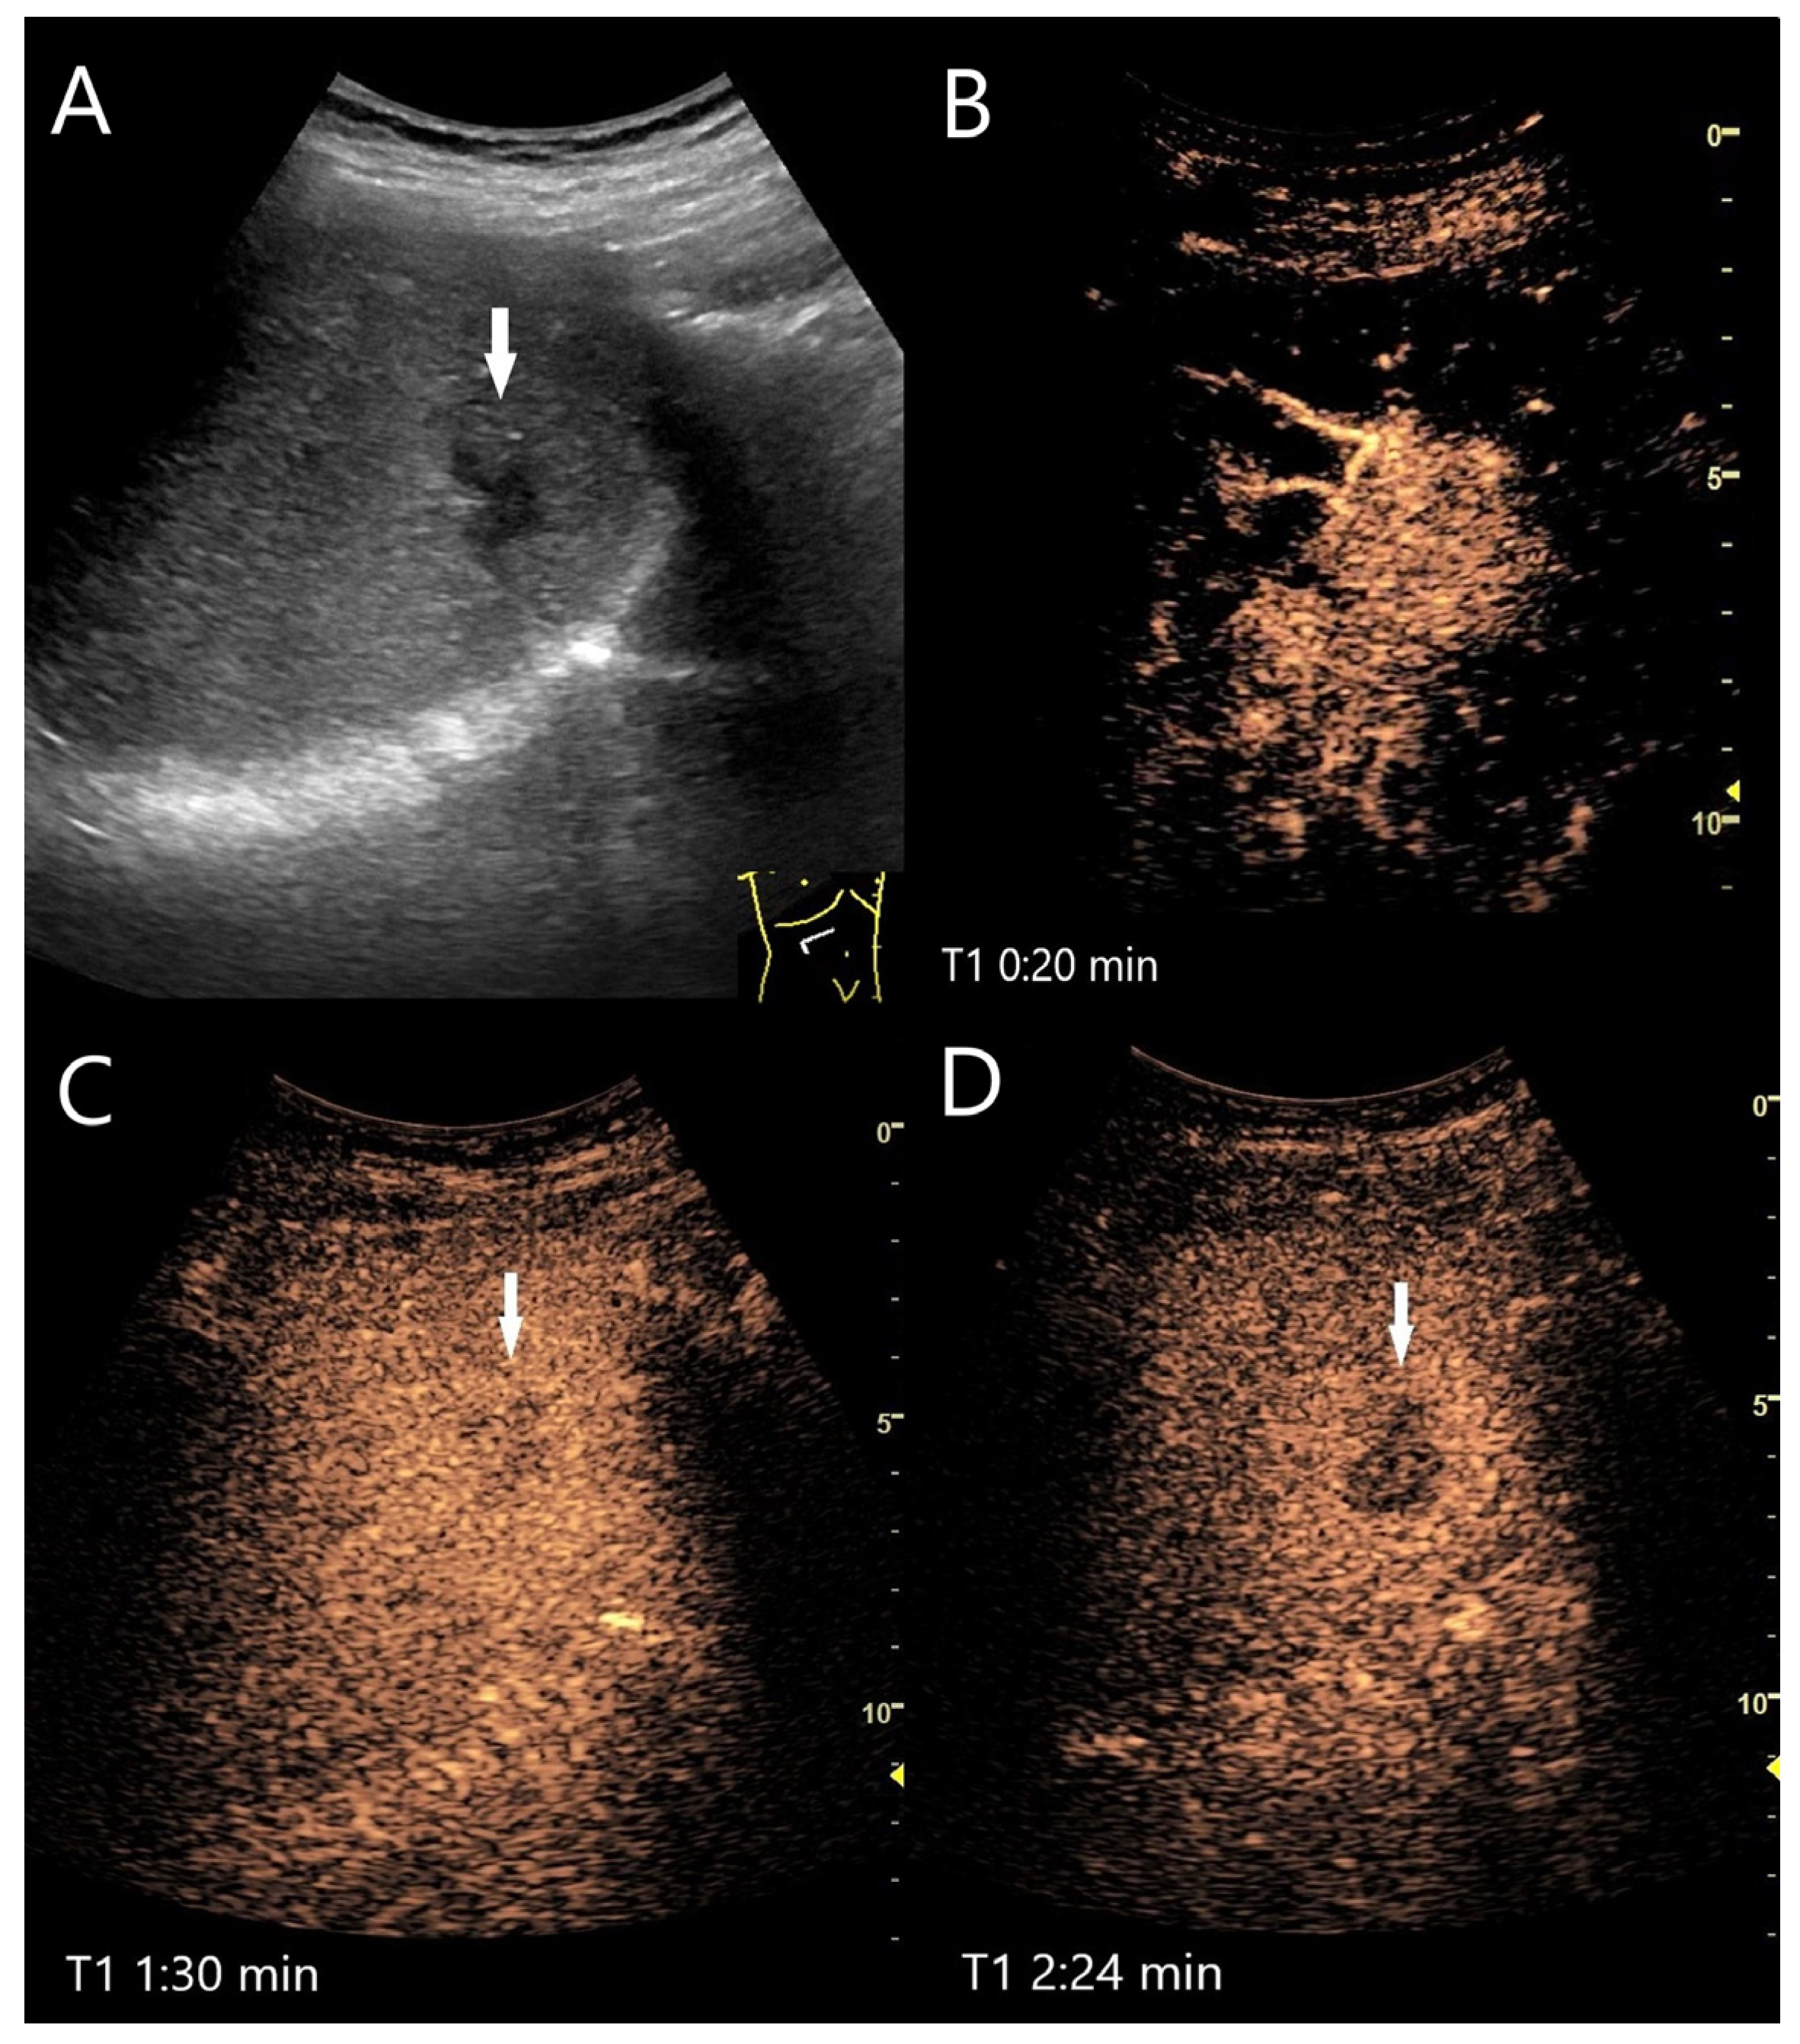

Various causes are discussed for washout in hemangiomas with hypoenhancement in the LP. The first one is caused by a technical aspect: UCA bubbles can be destroyed by too intense and prolonged exposure to ultrasound waves. If the ultrasound power (characterized by the Mechanical Index, MI) has been set too high, this further contributes to UCA bubble destruction. If hemangiomas fill up more slowly than in the surrounding liver parenchyma, the degree of disruption may be greater than the replenishment. It is, therefore, recommended that the ultrasound examination is not carried out continuously up to the 5th minute, but intermittently [16]. If an FLL possibly represents a hemangioma, we prefer a video loop in the AP and then every 30 or 60 s in the PVP and LP. However, in our experience, there are hemangiomas that still show a washout even with this procedure. A mild fade in the PVP and hypoenhancement in LP are described for hemangiomas with rapid onset [27]. In hemangiomas with rapid filling, it is debated whether the rapid filling has an equally rapid outflow, which in turn is more pronounced than the contrasting of the surrounding liver parenchyma [4]. Finally, fibrosis or scars lead to hypoenhancement during all contrast phases. Fibrosis in any type of lesion reduces the sinusoidal network, and thus, the vascular volume [4]. Hemangioma with a faint washout, in which fibrotic lesions have been described histologically, is demonstrated in Figure 2. A pronounced hypoenhancement in the LP of a hemangioma is shown in Figure 3.

Figure 2.

Partially fibrosed hemangioma. As part of a staging examination for adenocarcinoma of the gastro-esophageal junction, a 19 mm, smoothly bordered hyperechoic lesion (arrow) with an implied hypoechoic rim and punctate echogenic reflexes is diagnosed in the liver (A). On CEUS, the small lesion (between the markings) shows a marginal contrast image that is not completely smooth (B). In the PVP after 1:25 min, most of the lesion is enhanced, but slightly less than the surrounding parenchyma and with a small portion that is clearly hypoenhanced (C). After 3:04 min, the lesion is slightly hypoenhanced (D), while after 4:22 min (E) and 6:08 min (F), the lesion shows an unequivocal hypoenhancement. The lesion did not clearly correspond to a hemangioma on computed tomography either. This was the reason for a US-guided biopsy. Histology revealed a hemangioma, partially fibrosed and with tiny calcifications.